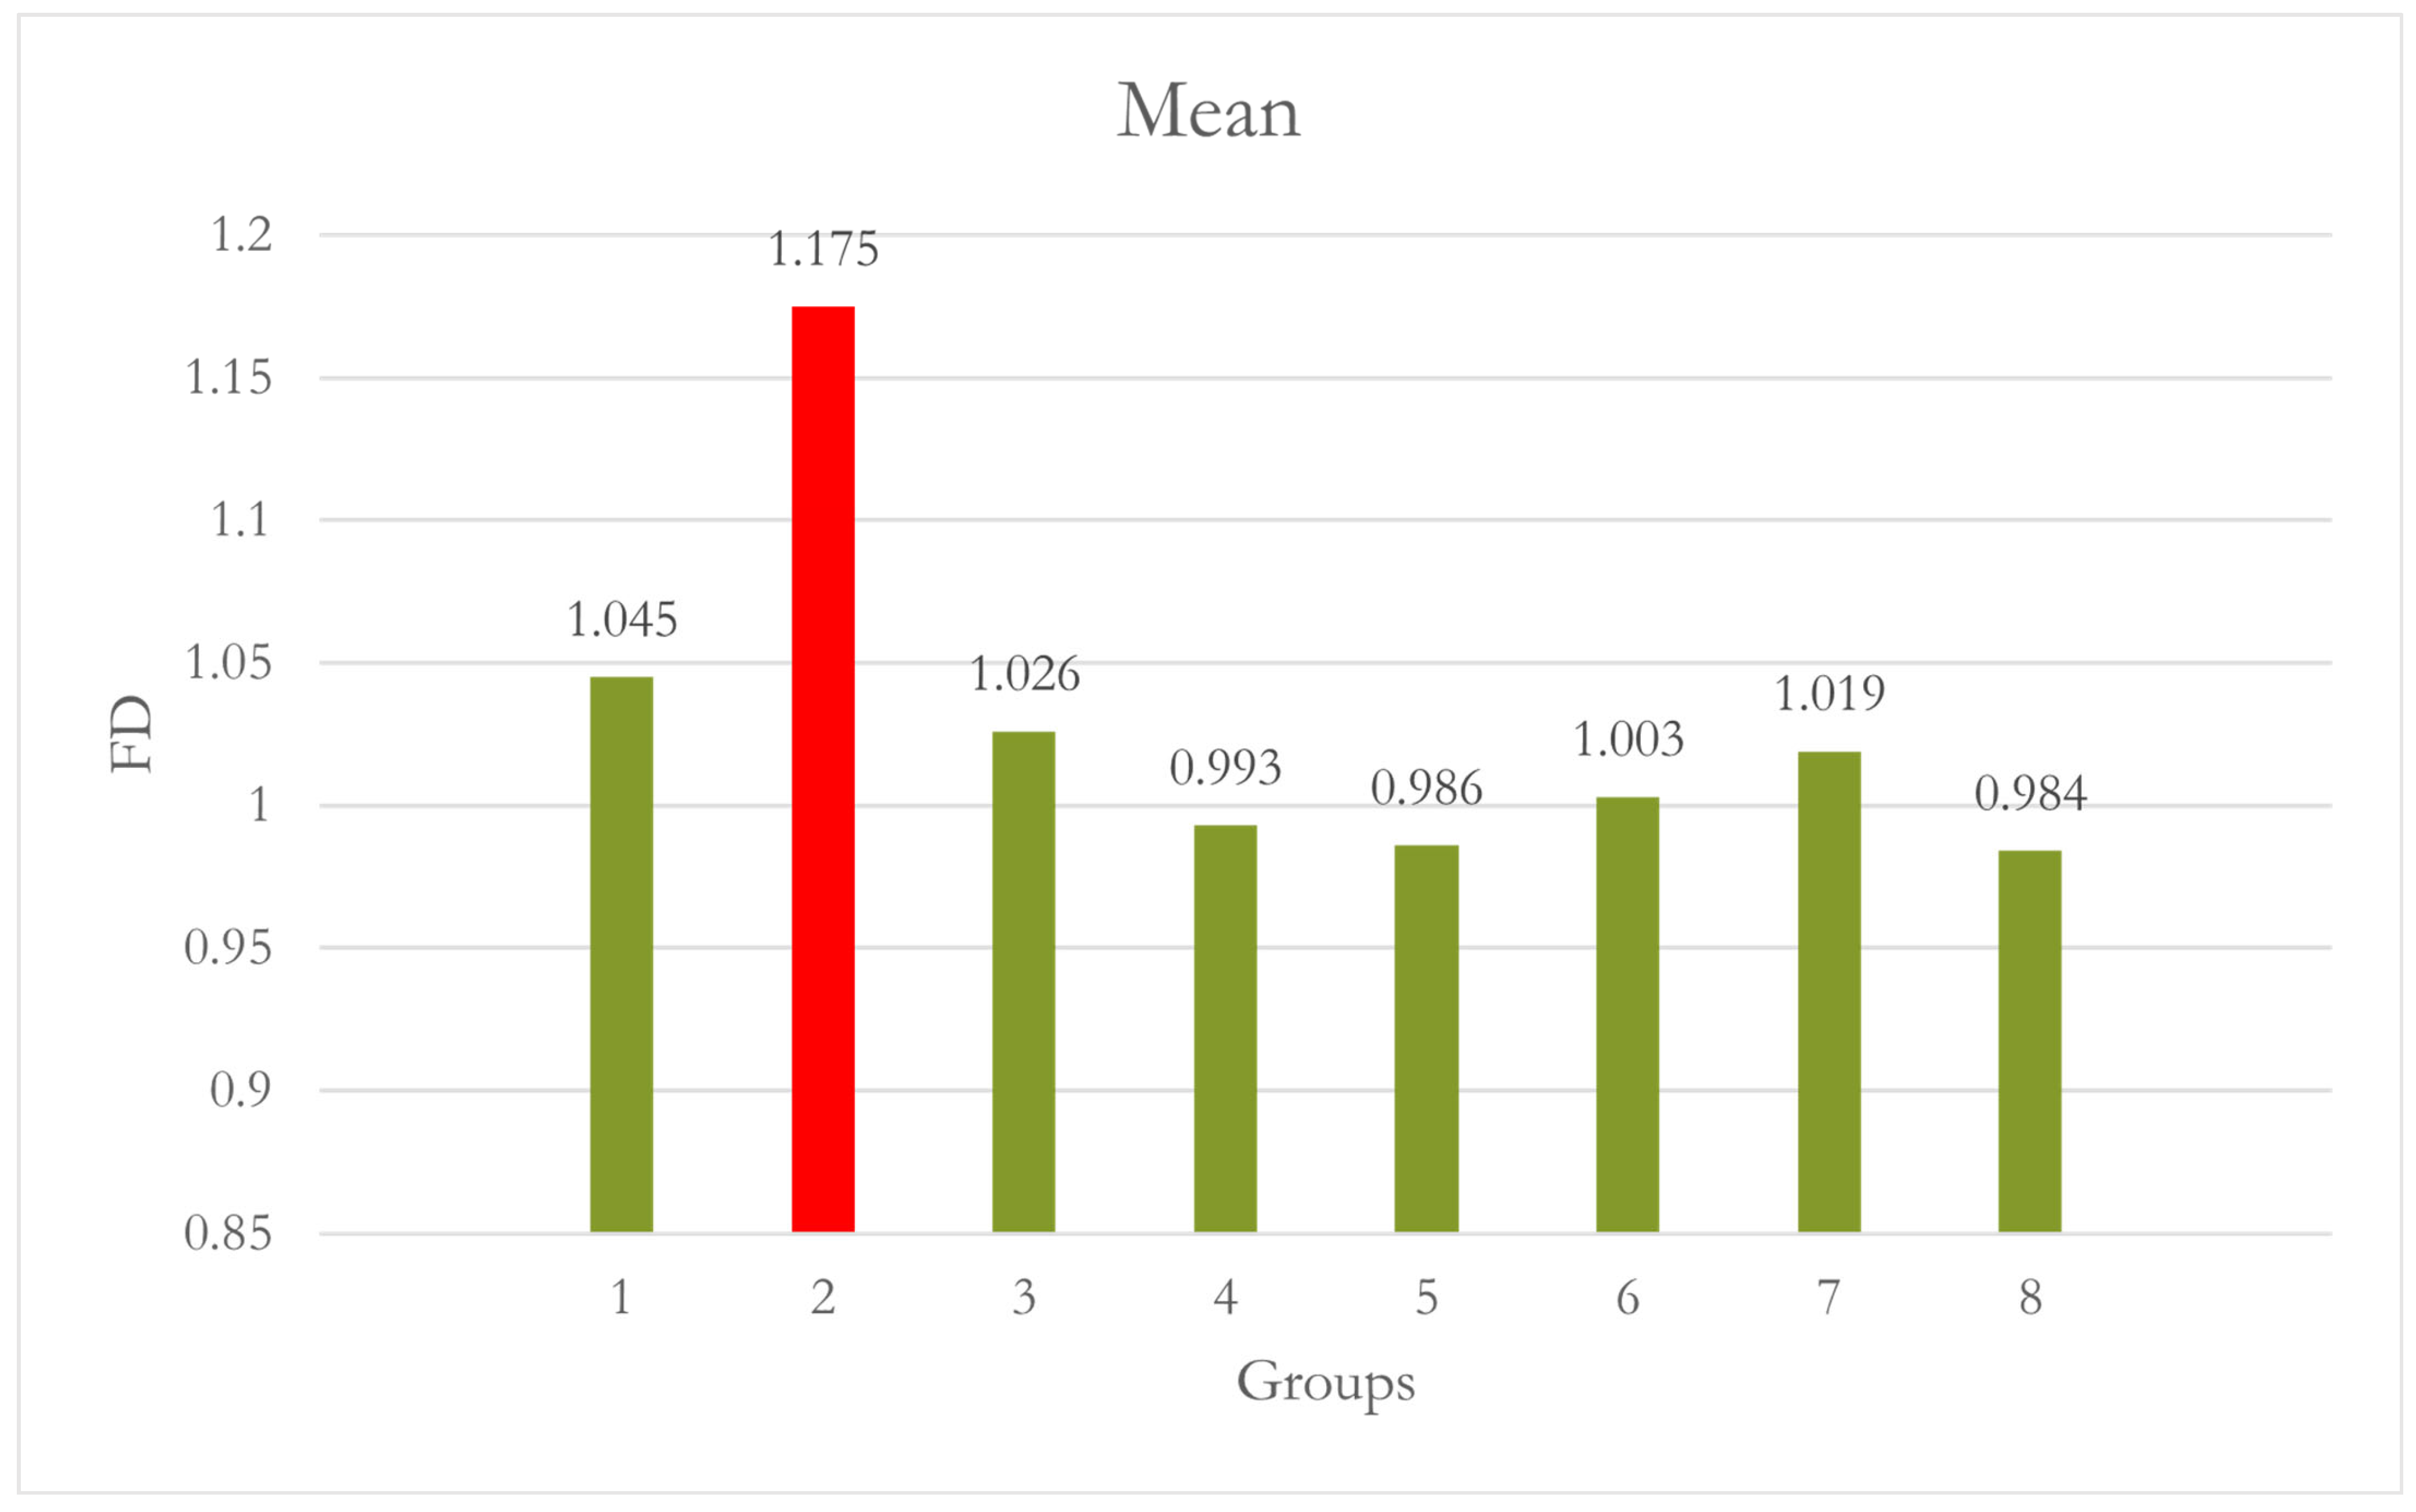

| Site 5 LM | 1 | 10 | 1.045 | 0.162 | 0.051 | 0.929 | 1.161 | 0.882 | 1.292 | - | 0.040 |

| 2 | 10 | 1.175 | 0.125 | 0.040 | 1.086 | 1.265 | 0.971 | 1.269 | 0.040 | - | |

| 3 | 10 | 1.026 | 0.094 | 0.030 | 0.959 | 1.093 | 0.949 | 1.265 | 1.000 | 0.010 | |

| 4 | 10 | 0.993 | 0.040 | 0.013 | 0.965 | 1.022 | 0.936 | 1.050 | 0.908 | 0.001 | |

| 5 | 10 | 0.986 | 0.048 | 0.015 | 0.952 | 1.021 | 0.920 | 1.052 | 0.838 | <0.001 | |

| 6 | 10 | 1.003 | 0.063 | 0.020 | 0.958 | 1.048 | 0.896 | 1.086 | 0.968 | 0.002 | |

| 7 | 10 | 1.019 | 0.068 | 0.021 | 0.970 | 1.067 | 0.928 | 1.118 | 0.998 | 0.006 | |

| 8 | 10 | 0.984 | 0.056 | 0.018 | 0.945 | 1.024 | 0.917 | 1.051 | 0.813 | <0.001 | |

| Total | 80 | 1.029 | 0.105 | 0.012 | 1.006 | 1.052 | 0.882 | 1.292 | |||